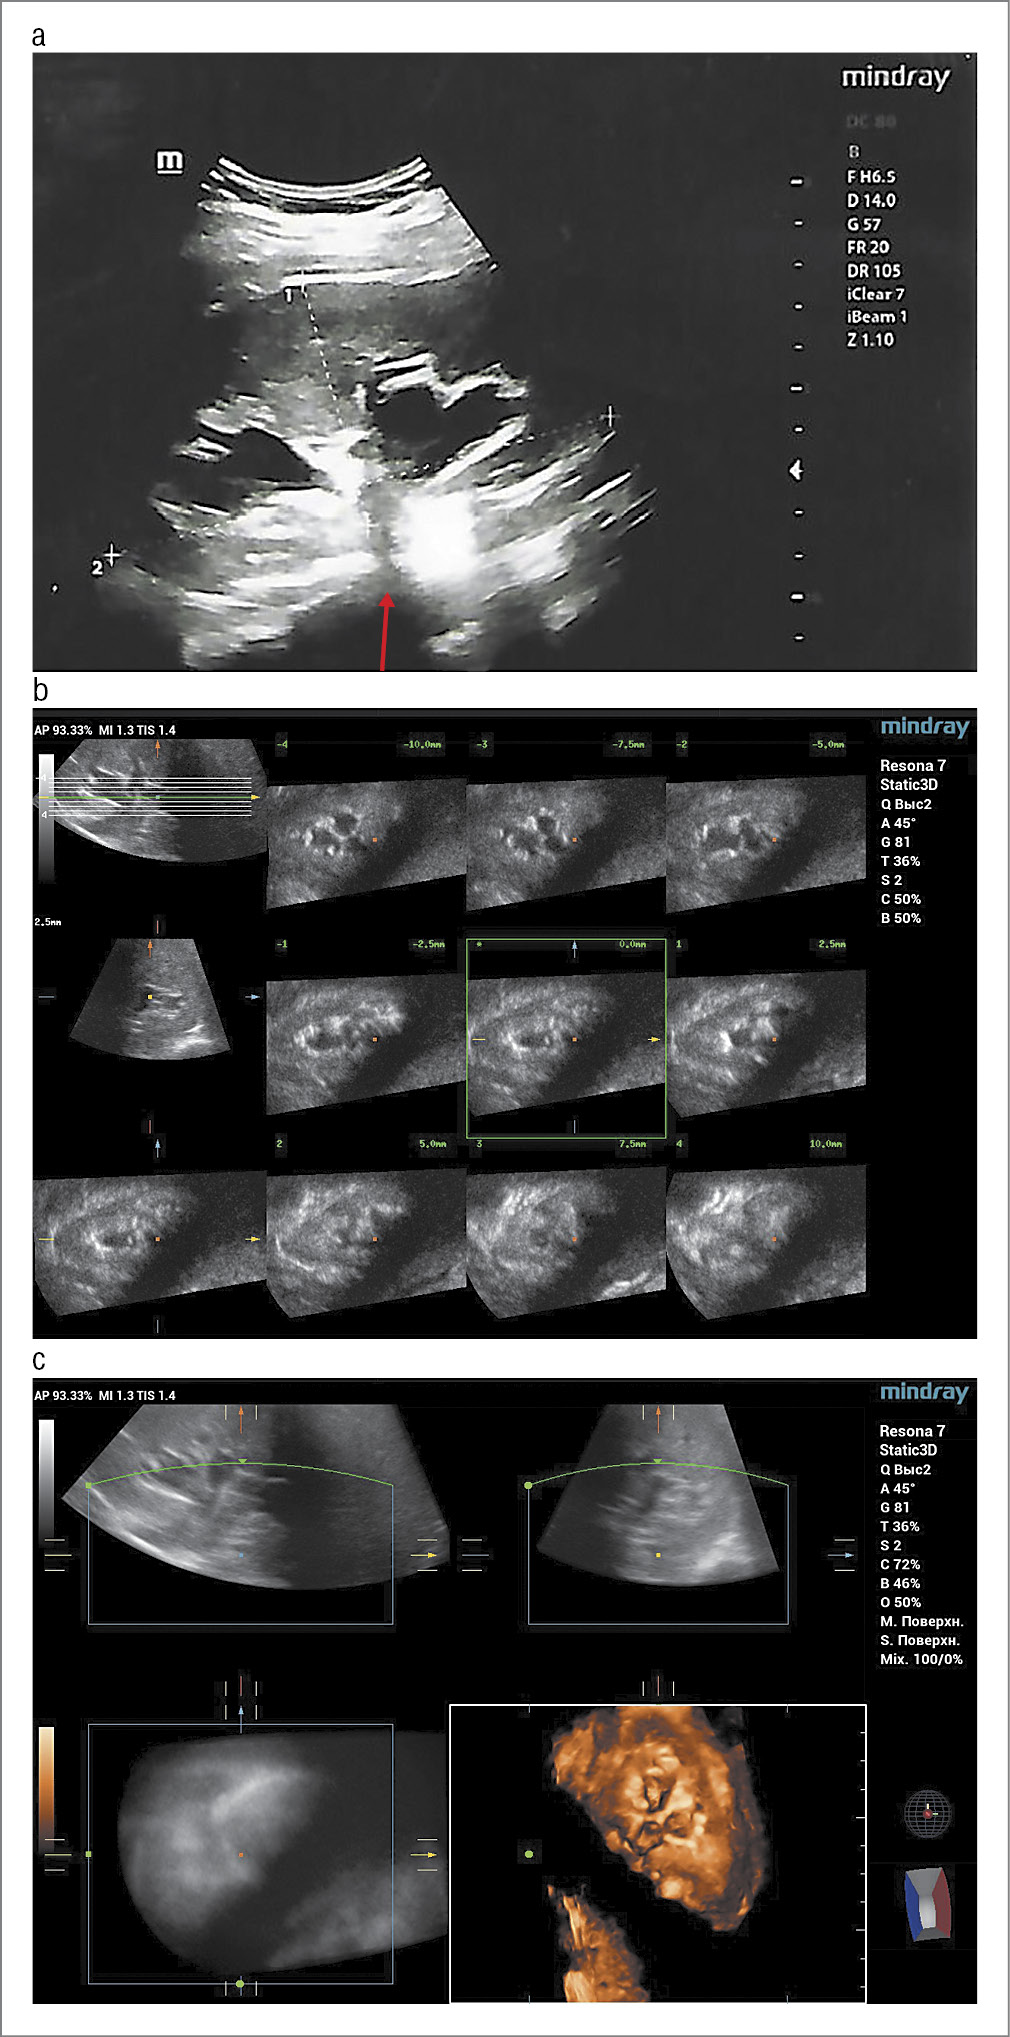

Рис. 1. Результаты эхографии. Случай 1: a – В-сканирование. Продольное изображение почки. Акустическая тень за конкрементом в чашке (указано стрелкой); b – 3D/4D-сканирование. Мультиплоскостной режим. Расширенные чашечки почки с обычной паренхимой в разных параллельных плоскостях; c – 3D/4D-сканирование. Мультиплановый режим сканирования. Почка без расширения лоханки и с деформацией чашечек.

Fig. 1. Sonogram. Case 1: a – B-scan. Longitudinal image of the kidney. Acoustic shadow behind the calculus in the calyx (indicated by the arrow); b – 3D/4D scanning. Dilated kidney calyces with normal parenchyma in different parallel planes; c – 3D/4D scanning. Kidney without pelvic dilation and with calyx deformity.

Клиническое наблюдение 1

Беременная 35 лет (1-я беременность, 1-е роды) встала на учет по беременности до 12 нед. Беременность наступила на фоне ранее диагностированной эндометриоидной кисты правого яичника. Проведено обследование согласно приказу Минздрава России от 20.10.2020 №1130н. В I триместре обнаружен генотип ДНК вируса папилломы человека – ВПЧ (тип 51) – 7,4 lg/105 клеток. Цитограмма с патологией плоского эпителия L-SIL (HPV). Коэкспрессия онкобелков p16/Ki67 не обнаружена (низкая вероятность H-SIL, рекомендации по результатам ВПЧ-ПАП-теста). При проведении эхографии в I триместре выявлена эндометриоидная киста правого яичника. Данные скрининга I триместра не указывали на повышенные риски хромосомных аномалий, выявлены низкие риски развития ранней и поздней преэклампсии. Эхография плода во II триместре – без особенностей. На 28-й неделе женщина предъявила жалобы на тянущую боль в области поясницы слева, иррадиирующую по внутренней поверхности бедра. Проведено эхографическое исследование почек. В средней чашке левой почки выявлен гиперэхогенный компонент до 5 мм в диаметре, дающий акустическую тень. Заключение: мочекаменная болезнь (рис. 1). В общем анализе мочи выявлены незначительная гематурия, соли оксалаты, лейкоциты до 15 в поле зрения, эпителий плоский до 25 в поле зрения, цилиндры и белок не обнаружены. Болевой синдром купирован при помощи спазмолитических и противовоспалительных средств. На 36-й неделе произошло преждевременное излитие околоплодных вод. Родилась девочка 2800 г и 45 см, с оценкой по шкале Апгар 7/7 баллов. В первые сутки жизни отмечены синдром дыхательных расстройств, подозрение на внутриутробную пневмонию. Проведен курс антибиотикотерапии у ребенка с положительным эффектом, женщина выписана с положительным эффектом на 12-е сутки. В послеродовом периоде произведено эхографическое исследование почек, по результатам которого выявлены признаки мочекаменной болезни. Признаков ОУ не выявлено.